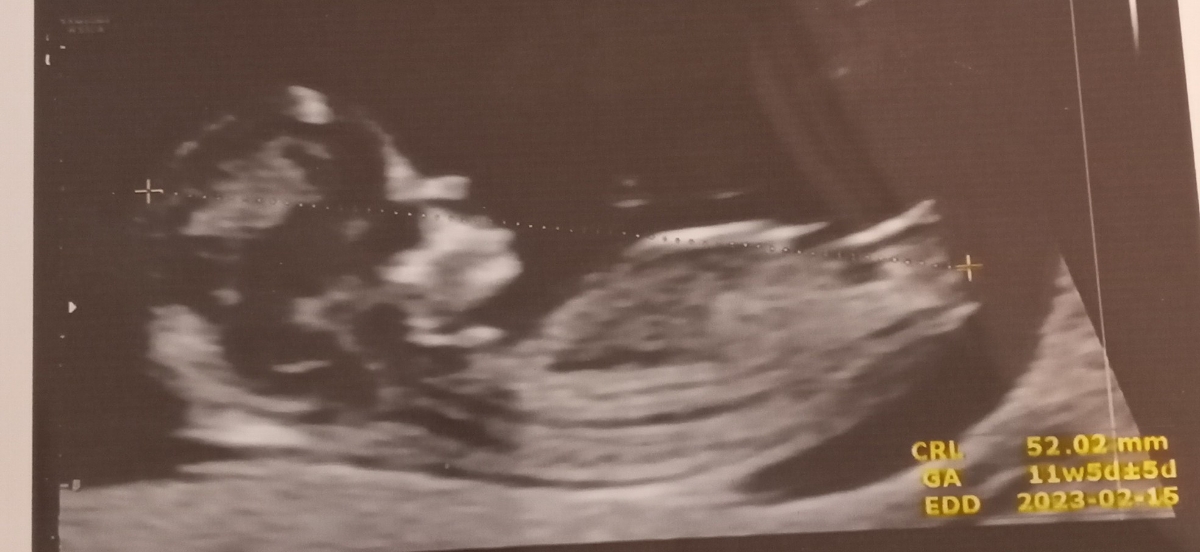

سلام. من تاریخ اخرین پریودم ۱۸ اردی بهشت بوده ولی طبق سونوگرافی ان تی، در تاریخ ۱۰ مرداد ۱۱ هفته ۵ روز بودم.

اوما منو زده هفته ۱۶ ولی طبق سونوی ان تیم من الان ۱۴ هفته ۶ روز هستم.

عزیزم طبق هر دو سونوگرافی حدودا 15 هفته و 2 الی 4 روز هستید، بر همین اساس پیش

بروید و سونوگرافی آنومالی اسکن را در هفته 18 انجام دهید 🌹